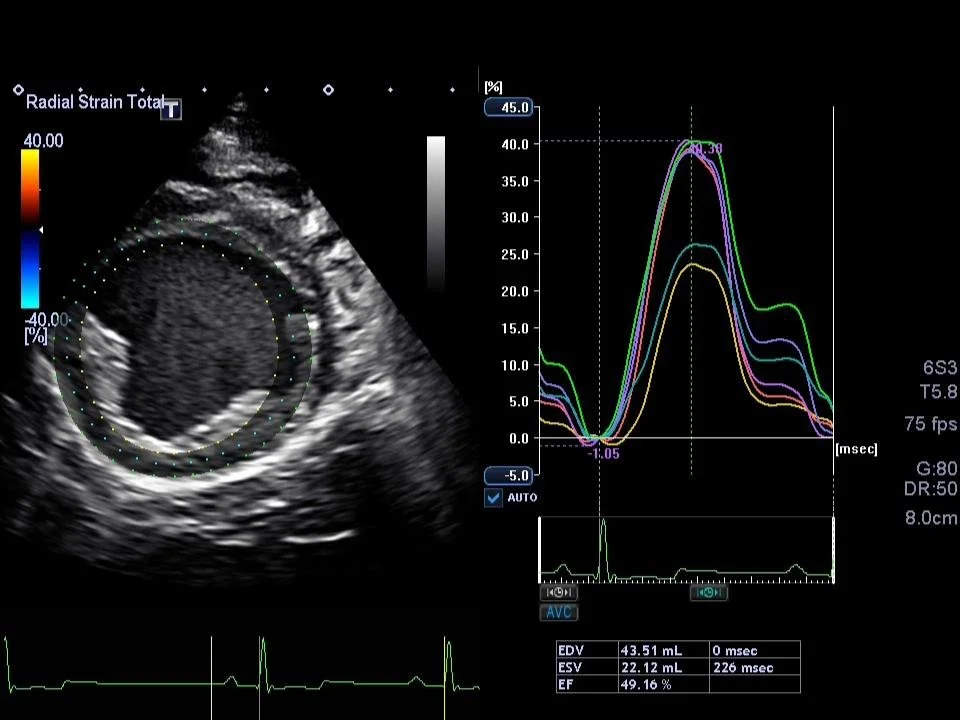

Echocardiograms

A non-invasive ultrasound of the heart that evaluates cardiac structure and function in real time.